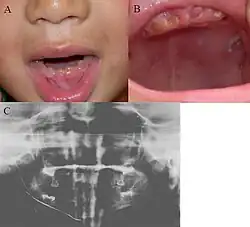

| Oral photographs from an individual with Dentinogenesis imperfecta | |

People with this condition have abnormal enamel, short and narrow roots, and can lack nerves. This condition can cause teeth to be discolored (most often a blue-gray or yellow-brown color) and translucent, giving teeth an opalescent sheen.[2][3][8][5][9] Teeth are also less mineralized than normal, making them prone to rapid wear, breakage, and loss.[2][3][4][5][8] These problems can affect primary (baby) teeth alone, or both baby teeth and permanent (adult) teeth, with the primary teeth usually more severely affected.[5][8]

- Discolored teeth - teeth may be amber, brown, blue or opalescent

- Bulbous shape to the tooth crown due to cervical constriction

- Tooth wear/Non-carious tooth surface loss (NCTSL) - due to the poorly mineralized dentin, the enamel of the tooth is unsupported and subsequently shears or chips off as it is subjected to occlusal (biting) forces. This exposes the underlying less mineralized dentin which is less resistant to wear. Therefore, features of abrasion and attrition may become apparent.

The primary (baby) teeth are usually more severely affected than permanent (adult) teeth.[3][5][8]

Enamel is usually lost early because it is further inclined to attrition due to loss of scalloping at the dentinoenamel junction (DEJ). It was suggested that the scalloping is beneficial for the mechanical properties of teeth as it reinforces the junction between enamel and dentin.[15] However, the teeth are not more susceptible to dental caries than normal ones.